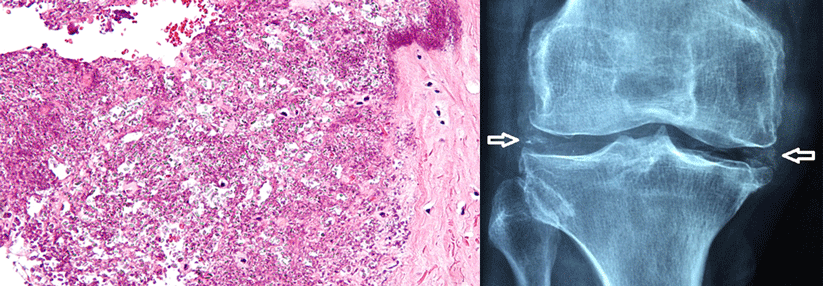

Zentrales Behandlungsziel bei Gicht ist heute, den Serum-Harnsäurespiegel unter 357 μmol/l (6 mg/dl)zu senken. So lautet die entsprechende EULAR*-Empfehlung. Mit weniger als 297 μmol/l (­­5 ­mg/dl) noch strenger ist die Vorgabe, wenn der Patient eine ausgeprägte Gicht mit Tophi, chronischer Arthropathie oder häufigen Anfällen hat, berichtete Professor Dr. Tillmann­ Uhlig­ vom Diakon­hjemmet Hospital in Oslo­.

Für den überwiegenden Teil der Gichtpatienten lassen sich diese Werte tatsächlich erreichen – sofern die Kranken intensiv betreut werden und man sie aktiv zur Therapie anleitet, so Prof. Uhlig­. Als Beispiel führte er NOR-Gout an, eine über zwei Jahre laufende Beobachtungsstudie mit…